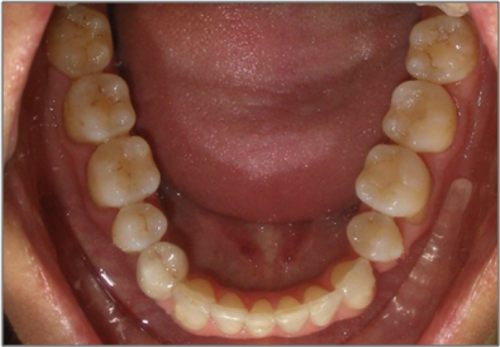

44 year old female:

Diagnosis:

- Upper and lower arch collapse due to missing teeth

- Retrusive angulation of upper & lower front teeth

- Severe collision and wear of front teeth

Treatment:

- Combination of Invisalign and braces

- Creating space for placement of an implant in the lower arch

- 28 months